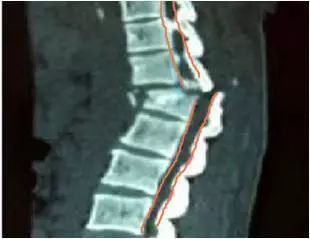

脊柱由颈椎、胸椎、腰椎和骶尾椎组成。除了支撑作用,脊椎也有保护脊髓的作用。脊椎中央有一个椎孔,负责传导大脑神经信号的脊髓就走行于椎孔内(如图3所示)。当脊柱损伤时(如图4所示),因结构改变,炎症水肿等因素导致椎孔狭窄,压迫脊髓导致受控区域活动障碍,这就是人们常说的截瘫。

图4

颈椎骨折后,颈椎的连续性受到破坏(如图4),如果搬运时出现弯折或扭曲,或者纵向受力,很容易出现骨折处移位,加重损伤,也就是我们所说的二次损伤。故事里前两个病人经专业人员处理,预后很好,但第三个病人经旁人粗暴处理后,出现严重后果。